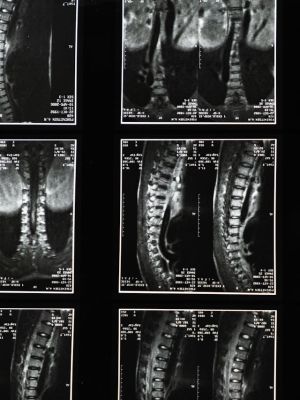

MR snimanje kičmeMR snimanje kičme

U klinici Balkan Medic magnetna rezonanca kičme izvodi se uz savremenu opremu i stručnost iskusnih lekara, pružajući precizne slike pršljenova, diskova, nerava i mekih tkiva.

Magnetna rezonanca kičme je savremeni, neinvazivni dijagnostički pregled kojim se pomoću snažnog magnetnog polja i radio-talasa dobijaju detaljne, slojevite slike kičmenog stuba i okolnih mekih tkiva. Ova metoda ne koristi štetno zračenje i potpuno je bezbolna. Prikaz je veoma precizan - mogu se jasno videti pršljenovi, međupršljenski diskovi, kičmena moždina i nervi, što lekarima omogućava da tačno utvrde uzrok tegoba. U ustanovi Balkan Medic, pregled magnetnom rezonancom kičme izvodi iskusan tim stručnjaka uz upotrebu savremene opreme, pa se pacijentu obezbeđuje maksimalna sigurnost i komfor tokom pregleda.